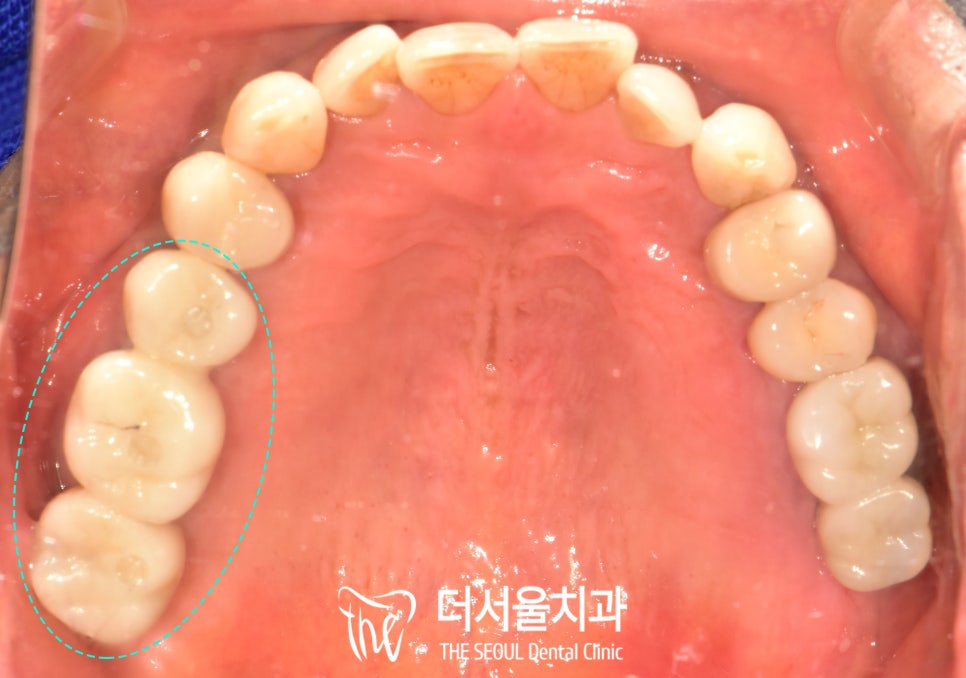

구치부 교합에 맞추어

위아래 동시 수복까지

완료한 모습인데요,

인공치근을 구강 내로 연결하는 지대주와

크라운 모두 개인 맞춤형으로 제작하였기에

본인에게 딱 맞는 보철이

잘 올라간 것을 확인할 수 있습니다.

또한 보철의 종류는

내구성과 심미성이 뛰어난

지르코니아를 사용하여

외국에서도 잘 사용하실 수 있도록

도와드렸습니다.